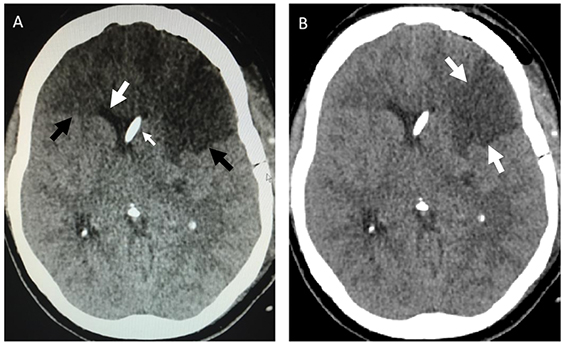

Box – Mobile phone photograph of the cranial computed tomography (CT) scan compared with the original image

A: Photograph of axial CT image sent via a mobile phone, showing apparent hypodense frontal lobes suggestive of infarction (black arrows). Note however the anterior horns of the lateral ventricles are not distorted or effaced, as would be expected with such an extensive infarct (large white arrow). A ventricular catheter is located in the right lateral ventricle (small white arrow). B: The original axial CT image showing only a wedge-shaped, left middle cerebral artery infarct (white arrows).

A 45-year-old woman presented with spontaneous subarachnoid haemorrhage secondary to a ruptured anterior communicating artery aneurysm. The anterior communicating artery aneurysm and an unruptured left middle cerebral artery aneurysm were clipped via craniotomy and a ventricular drain was inserted. Serial post-operative computed tomography (CT) brain scans showed an evolving infarction in the left middle cerebral artery territory, presumed to be secondary to temporary clipping at surgery, which became fully established after 28 hours. All cerebral vessels were patent, visualised on a post-operative CT angiogram. Elevated intracranial pressure (> 40 mmHg) and neurological fluctuation prompted a repeat CT scan, a photograph of which was taken from a computer screen using a mobile phone (Box, A). This image was sent by the intensive care unit consultant to the mobile phone of the on-call neurosurgeon, who noted apparent extensive bifrontal infarction. The patient was urgently transported to the operating room for decompressive craniectomy; however, on reviewing the scans at a radiology workstation before surgery (Box, B), the neurosurgeon noted the discrepancy and the procedure was cancelled. The patient recovered well and was neurologically intact and independent 6 months after discharge.

We confirmed that viewing angle-dependent reductions in luminance were responsible for the spurious frontal lobe darkening evident in the mobile phone image. Clearly, spatial variations in image brightness can dramatically affect image interpretation, with potentially disastrous results.